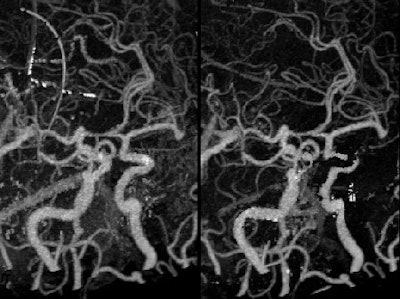

In this study of six patients, three with intracranial aneurysms and three with intracranial carotid stenosis, two aneurysms adjacent to the skull base were only partially visible in conventional CTA, but they were fully visible in dual-energy bone removal CTA. In the three cases of stenosis, conventional CTA failed to display the restricted vessels, while all intracranial stenotic lesions were visible on MIP images from dual-energy CT.

The dual-energy CT images were obtained using a Siemens Definition scanner at tube voltages of 80 kVp and 140 kVp, running software that registers the two-energy datasets and selectively removes bone structures. The 3D volume-rendered images and MIP images (with and without bone removal) were reviewed and compared with DSA.